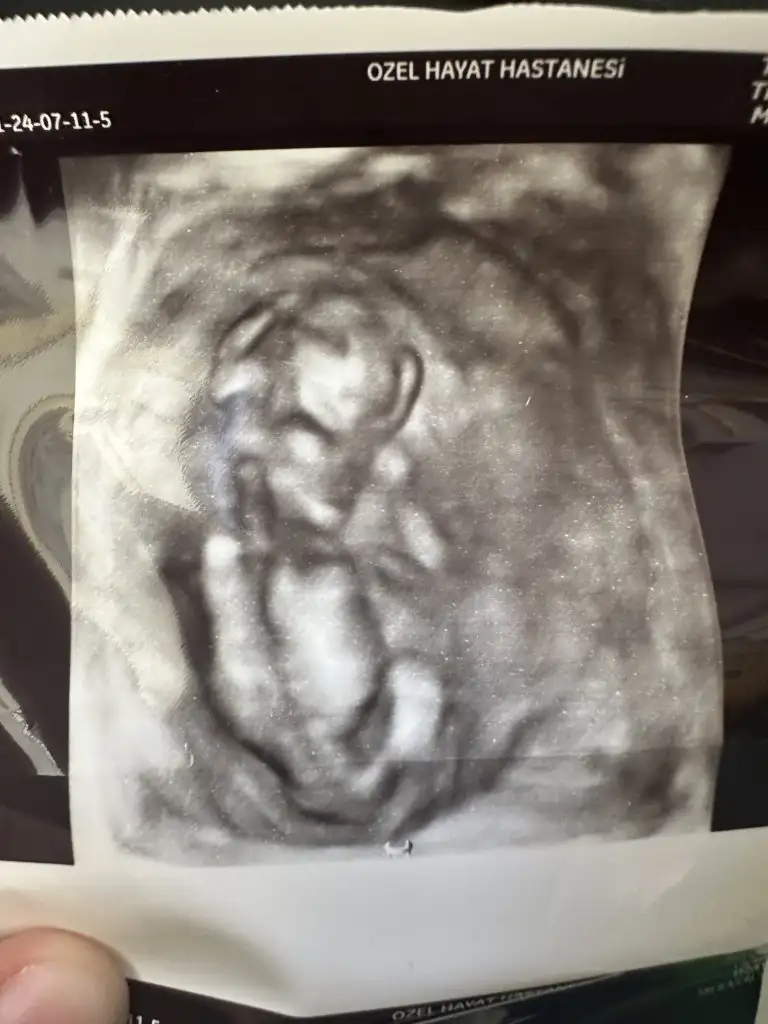

Az önce çekildik. 12+0 ız. Cinsiyet tahminleri nedir arkadaşlar?

• IMG_20240711_222412.webp

IMG_20240711_222412.webp

18,1 KB · Görüntüleme: 71

• IMG_20240711_222407.webp

IMG_20240711_222407.webp

17,7 KB · Görüntüleme: 75

• IMG_20240711_222357.webp

IMG_20240711_222357.webp

18 KB · Görüntüleme: 65